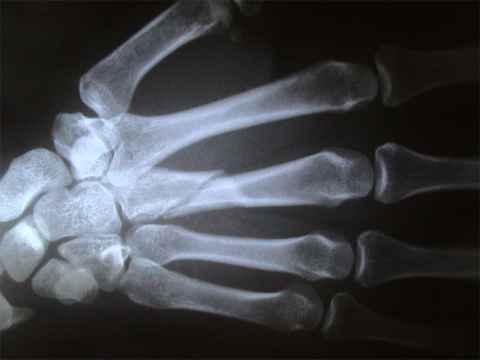

A su llegada aquí se le realiza el estudio Rx. y se le diagnostica fractura del tercer meta carpiano de la mano derecha.

Alli tienen los registros grafícos